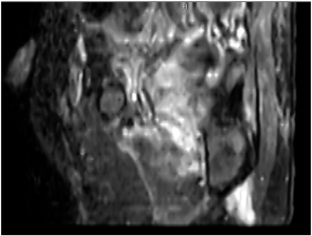

Fifty-six wheelchair-dependent adults with SCI of at least 1 month’s duration underwent pelvic sagittal STIR MRI screening. DTI-positive sites were defined by signal changes in subcutaneous fat or muscle. Ultrasonography, body composition, seating-related variables, and laboratory data were collected concurrently. Univariate and multivariate logistic-regression analyses identified independent risk factors.

MRI detected subclinical DTI in 33 of 112 ischial regions (29.5%). Ultrasonography was concordant in only 15 sites (45.5%). Multivariable analysis showed that longer daily wheelchair use (p = 0.018), greater subcutaneous-tissue thickness at the ischial tuberosities (p = 0.028), and less-frequent pressure-relief manoeuvres (p = 0.031; protective) were independently associated with DTI. BMI, peak interface pressure, and routine haematologic or nutritional markers were not significant.

MRI screening revealed subclinical DTI in nearly one-third of wheelchair-dependent patients with SCI and outperformed ultrasonography for early detection. Extended sitting time, thicker subcutaneous fat at the ischial tuberosity, and infrequent pressure relief emerged as modifiable risk factors. A risk-based MRI surveillance strategy may enable timely preventive interventions and reduce progression to overt pressure ulcers.